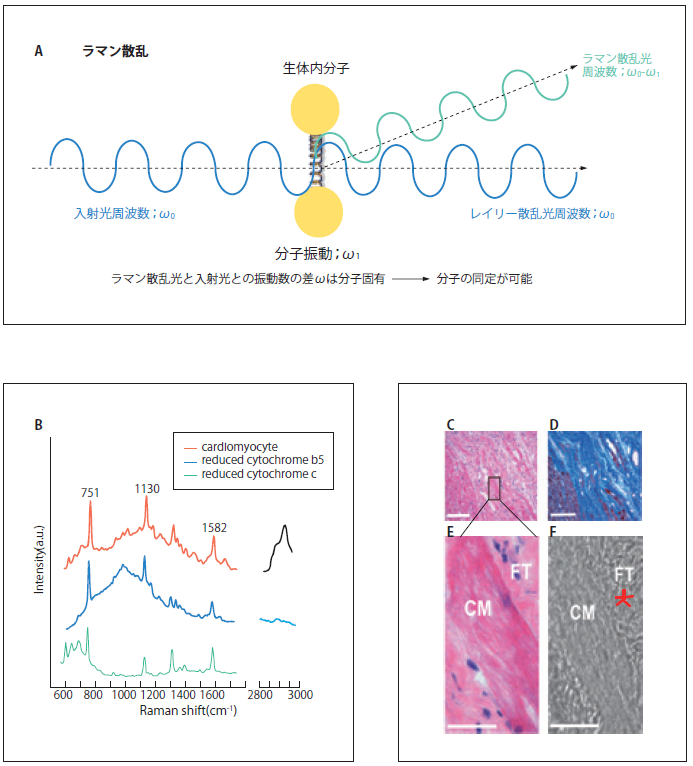

ラマン散乱光による心筋梗塞イメージング

光を物質に照射するとその一部は散乱される。散乱光の大半は入射光と同じ波長を示すが、一部は入射光と波長が異なる。この異なった波長の散乱光をラマン散乱と呼ぶが、波長のシフト量はその物質を構成する分子構造に固有であるため、測定されたラマンスペクトルを解析することにより構成分子の同定が可能である。すなわち、ラマン散乱分光は、生きた細胞・組織中に存在する分子の構造やその変化を非破壊・プローブなしで解析可能であり、in vivo診断に適した分光法といえる12)。しかし、ラマン散乱の散乱断面積は非常に小さいため、定点での解析に用いられることはあってもイメージングはほぼ不可能であったため、ラマン分光法は医学・生物学の領域であまり用いられてこなかった。

近年、光学技術の急速な発展により、生理的な環境下でかつ十分な速度でラマンイメージングを行えるシステムが登場してきており、ラマン分光法を生体機能解析に利用する道が拓けてきた13)。我々は、同時に多点の測定が可能なライン照明とパラレル検出技術を取り入れた高速ラマン散乱顕微鏡システムを用いている14)。つまり、532 nm励起によるチトクロームの共鳴ラマン散乱を利用し、主成分分析によるイメージ再構築を行うことにより、無標識でラット心臓(正常・陳旧性心筋梗塞巣)の生体組織診断が可能であることを示した(図3B-I)。この技術を用いて、我々はin vivo無標識生体組織診断を目指している。

図3 ラマン散乱光による心筋梗塞イメージング

A)ラマン散乱の模式図。物質に光を入射したとき、入射光は違う波長で散乱される光をラマン散乱光という。このラマン散乱光は分子固有の分子振動に依存するため、ラマン散乱光を分光することで、分子の同定、構造を推定することが可能。B)心筋細胞のラマンスペクトル。心筋細胞のラマンスペクトルは還元型b5及びc型チトクロームの寄与が大きい。C) HE染色による心筋梗塞の境界領域イメージ。D) 線維染色による心筋梗塞の境界領域イメージ。E)Cのボックス領域の拡大イメージ。F)白色光イメージ。G)Fの線維性の組織(星印)とI型コラーゲンのラマンスペクトルの比較。H)Eの領域についてラマンスペクトル測定後、主成分分析した時の第2主成分ラマンイメージ。I) 主成分分析を適用した時の第2主成分ローディングプロット。正のバンドは還元型b5及びc型チトクローム(751, 1130,1582 cm-1)及び脂質(2854 cm-1)に関連。負のバンドはI型コラーゲン(857, 1250, 2945 cm-1)に関連。スケールバーは50µm(C, D);20 µm(E, F, H)。CM、ラット心筋細胞。